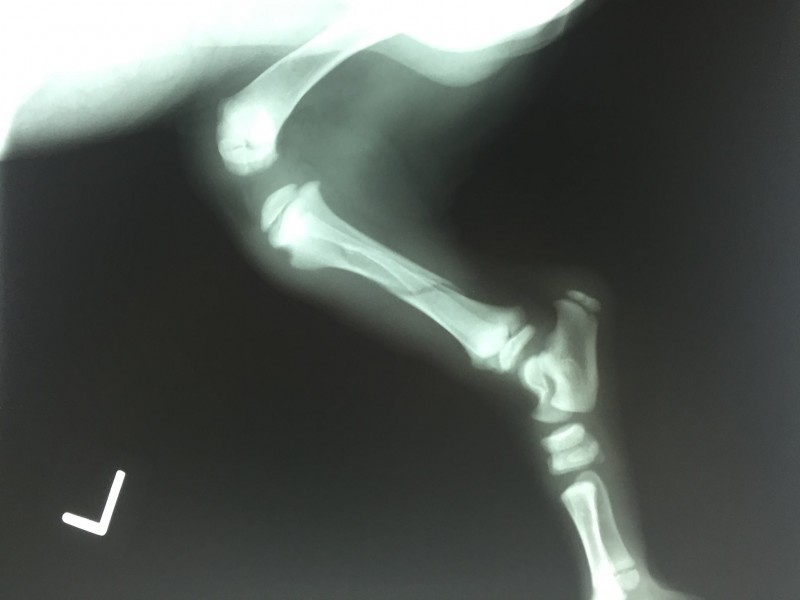

BHRR’s Bookers latest x-ray

BHRR’s Booker VIDEO – 3 month old DDB with a back broken leg(Tibia & Fibula Affected)

January 16th, 2018 This is a short video taken after his latest cast was removed today.

Unfortunately, this is his leg….

*He leg was broken December 8th @ 8 weeks of age

*He was not seen by a Vet until the 9th so proper treatment was not immediately given

*He had then been put in a temporary cast that had not been properly placed

*Then the cast had not been changed weekly, with assessments/x-Rays NOR was surgery given to repair the leg

*By time we were asked to assist arriving to BHRR December 23rd and we got him in immediately to see our own Vet & Specialist Team, surgery was no longer considered the best option.

*So, weekly Vet visits, regular x-rays and cast changes were being done

*From his first Vet Visit here on December 27th, concern was had over his ankle due to the improper placement of the first cast plus lack of weekly x-Rays & cast replacements being done. Corrections were made to all future weekly cast placements under our care to work to ensure proper healing was happening

*January 16th’s x-rays indicate that his leg continues to heal slowly and well where the breaks are. However, the integrity to that ankle is still compromised.

*Though, his breaks are not fully healed, we need to shift the focus to his ankle and the recommendations have been to keep a cast off for the next two weeks and work on rehabilitation with the ankle and working on him planting his foot/leg into a normal walking/standing position

*He also remains having swollen toes that with removal of the cast the hope is that the swelling may successfully resolveHe has a long journey still ahead of him.